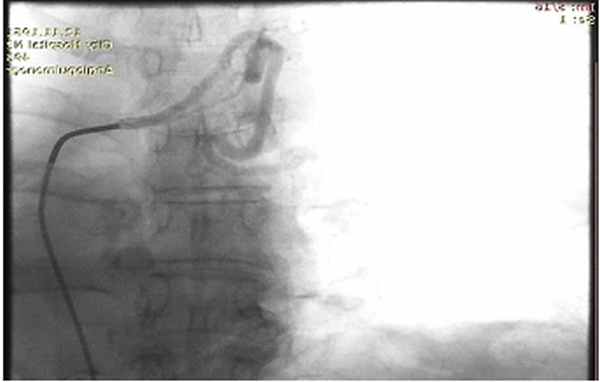

Ригидная бронхоскопия с клапанной бронхоблокацией правого верхнедолевого бронха

Патологически расширенная правая бронхиальная артерия

Учитывая вышеуказанное, диагностика легочного кровотечения, как правило, требует выполнения ригидной̆ бронхоскопии, позволяющие не только минимизировать риск развития асфиксии, но и выполнить ряд лечебных мероприятий. Выполняемая при ригидной бронхоскопии клапанная бронхоблокация позволяет добиться надежного временного гемостаза и практически полностью исключает риск развития фатальных осложнений.В случаях легочного кровотечения большего объема (2-3 ст.) выбор лечебной тактики зависит, как правило, от основного заболевания. Источником кровотечения из большого круга кровообращения служат бронхиальные артерии, являющиеся основой артериального кровоснабжения легочной паренхимы.

Видеоторакоскопическая расширенная комбинированная бронхопластическая лобэктомия у пациента с центральным раком левого легкого, осложненного легочным кровотечением Обычный диаметр этих артерий менее 1 мм. Любые визуализируемые по данным Ангио-КТ бронхиальные артерии могут считаться патологически расширенными. При легочных кровотечениях любого объема, с наличием патологических бронхиальных артерий, рентгенэндоваскулярные вмешательства могут быть методом выбора как дополнительной диагностики, так и радикального гемостаза.

Непосредственным методом гемостаза является эмболизация бронхиальных артерий. По данным литературы эффективность рентгенэндоваскулярной эмболиации бронхиальных артерий составляет около 97%.

Рис. 4. Селективная ангиография правой бронхиальной артерии у пациентки с доброкачественной метастазирующей лейомиомой и массивным КХ. а - увеличение диаметра и извитости артерии, выход контраста. б - картина после эмбо-лизации артерии.

Эмболизация бронхиальных артерий

Эмболизация бронхиальных артерий для терапии тяжелого КХ была впервые предложена J. Яету е1 а1. в 1974 г. [32, 33]. В настоящее время ЭБА позволяет добиться немедленного прекращения КХ у 80-90% больных (рис. 4), предотвратить рецидивы КХ в течение ближайшего месяца у 85% пациентов и в течение длительного времени - у 60% [34].

Противопоказано проведение ЭБА справа при отхож-дении передней средней спинальной артерии от правой межреберной артерии (риск параплегии) и слева - при наличии эзофагеальной ветви (риск некроза пищевода). В настоящее время техника с использованием микрокатетеров позволяет эмболизировать источники кровопотери на расстоянии от этих артериальных ответвлений [35].

В некоторых случаях артериография бывает неинформативной: при отсутствии гиперваскуляризации (причиной КХ служат поражения легочных артерий), неправильном положении катетера, визуализации спинальной ветви или после недавнего системного введения вазоконстрикторов (терлипрессина) [7].